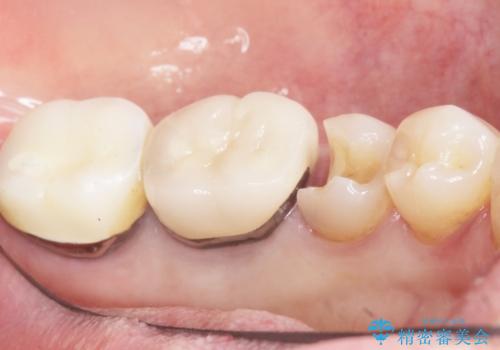

- 詰め物の境目が黒いことを気にされ、来院された患者様です。

精査したところ、左下の奥歯(左下5)のプラスチックの詰め物と歯の境目が虫歯になり、黒くなっていました。

古い詰め物とう蝕を除去し、審美的で適合が良く二次う蝕になりにくいセラミックインレーによる修復を行いました。